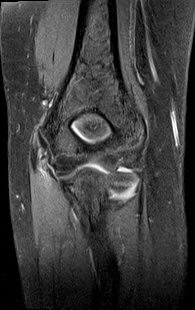

ÀÚ±â°ø¸í°Ë»ç

ÆÈ²ÞÄ¡ ̫̿ ÃøºÎÀÎ´ë ÆÄ¿­ ¹× °ß¿­°ñÀý(±×¸² 8, 9)